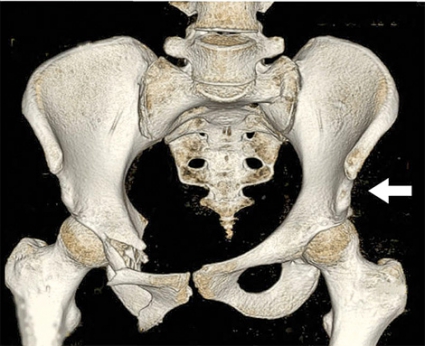

• Anteroposteriort genom direkt våld mot bakre spina alternativt os pubis eller genom utåtrotationsvåld via ena eller båda höftlederna, ledande till utåtrotation av bäckenhalvorna, »open book«-skada. Detta ses hos t ex förare av bil vid frontalkollision, hos fotgängare påkörd av bil, vid MC-olycka eller vid ridolycka då ryttare faller baklänges med hästen över sig (Figur 4, överst).